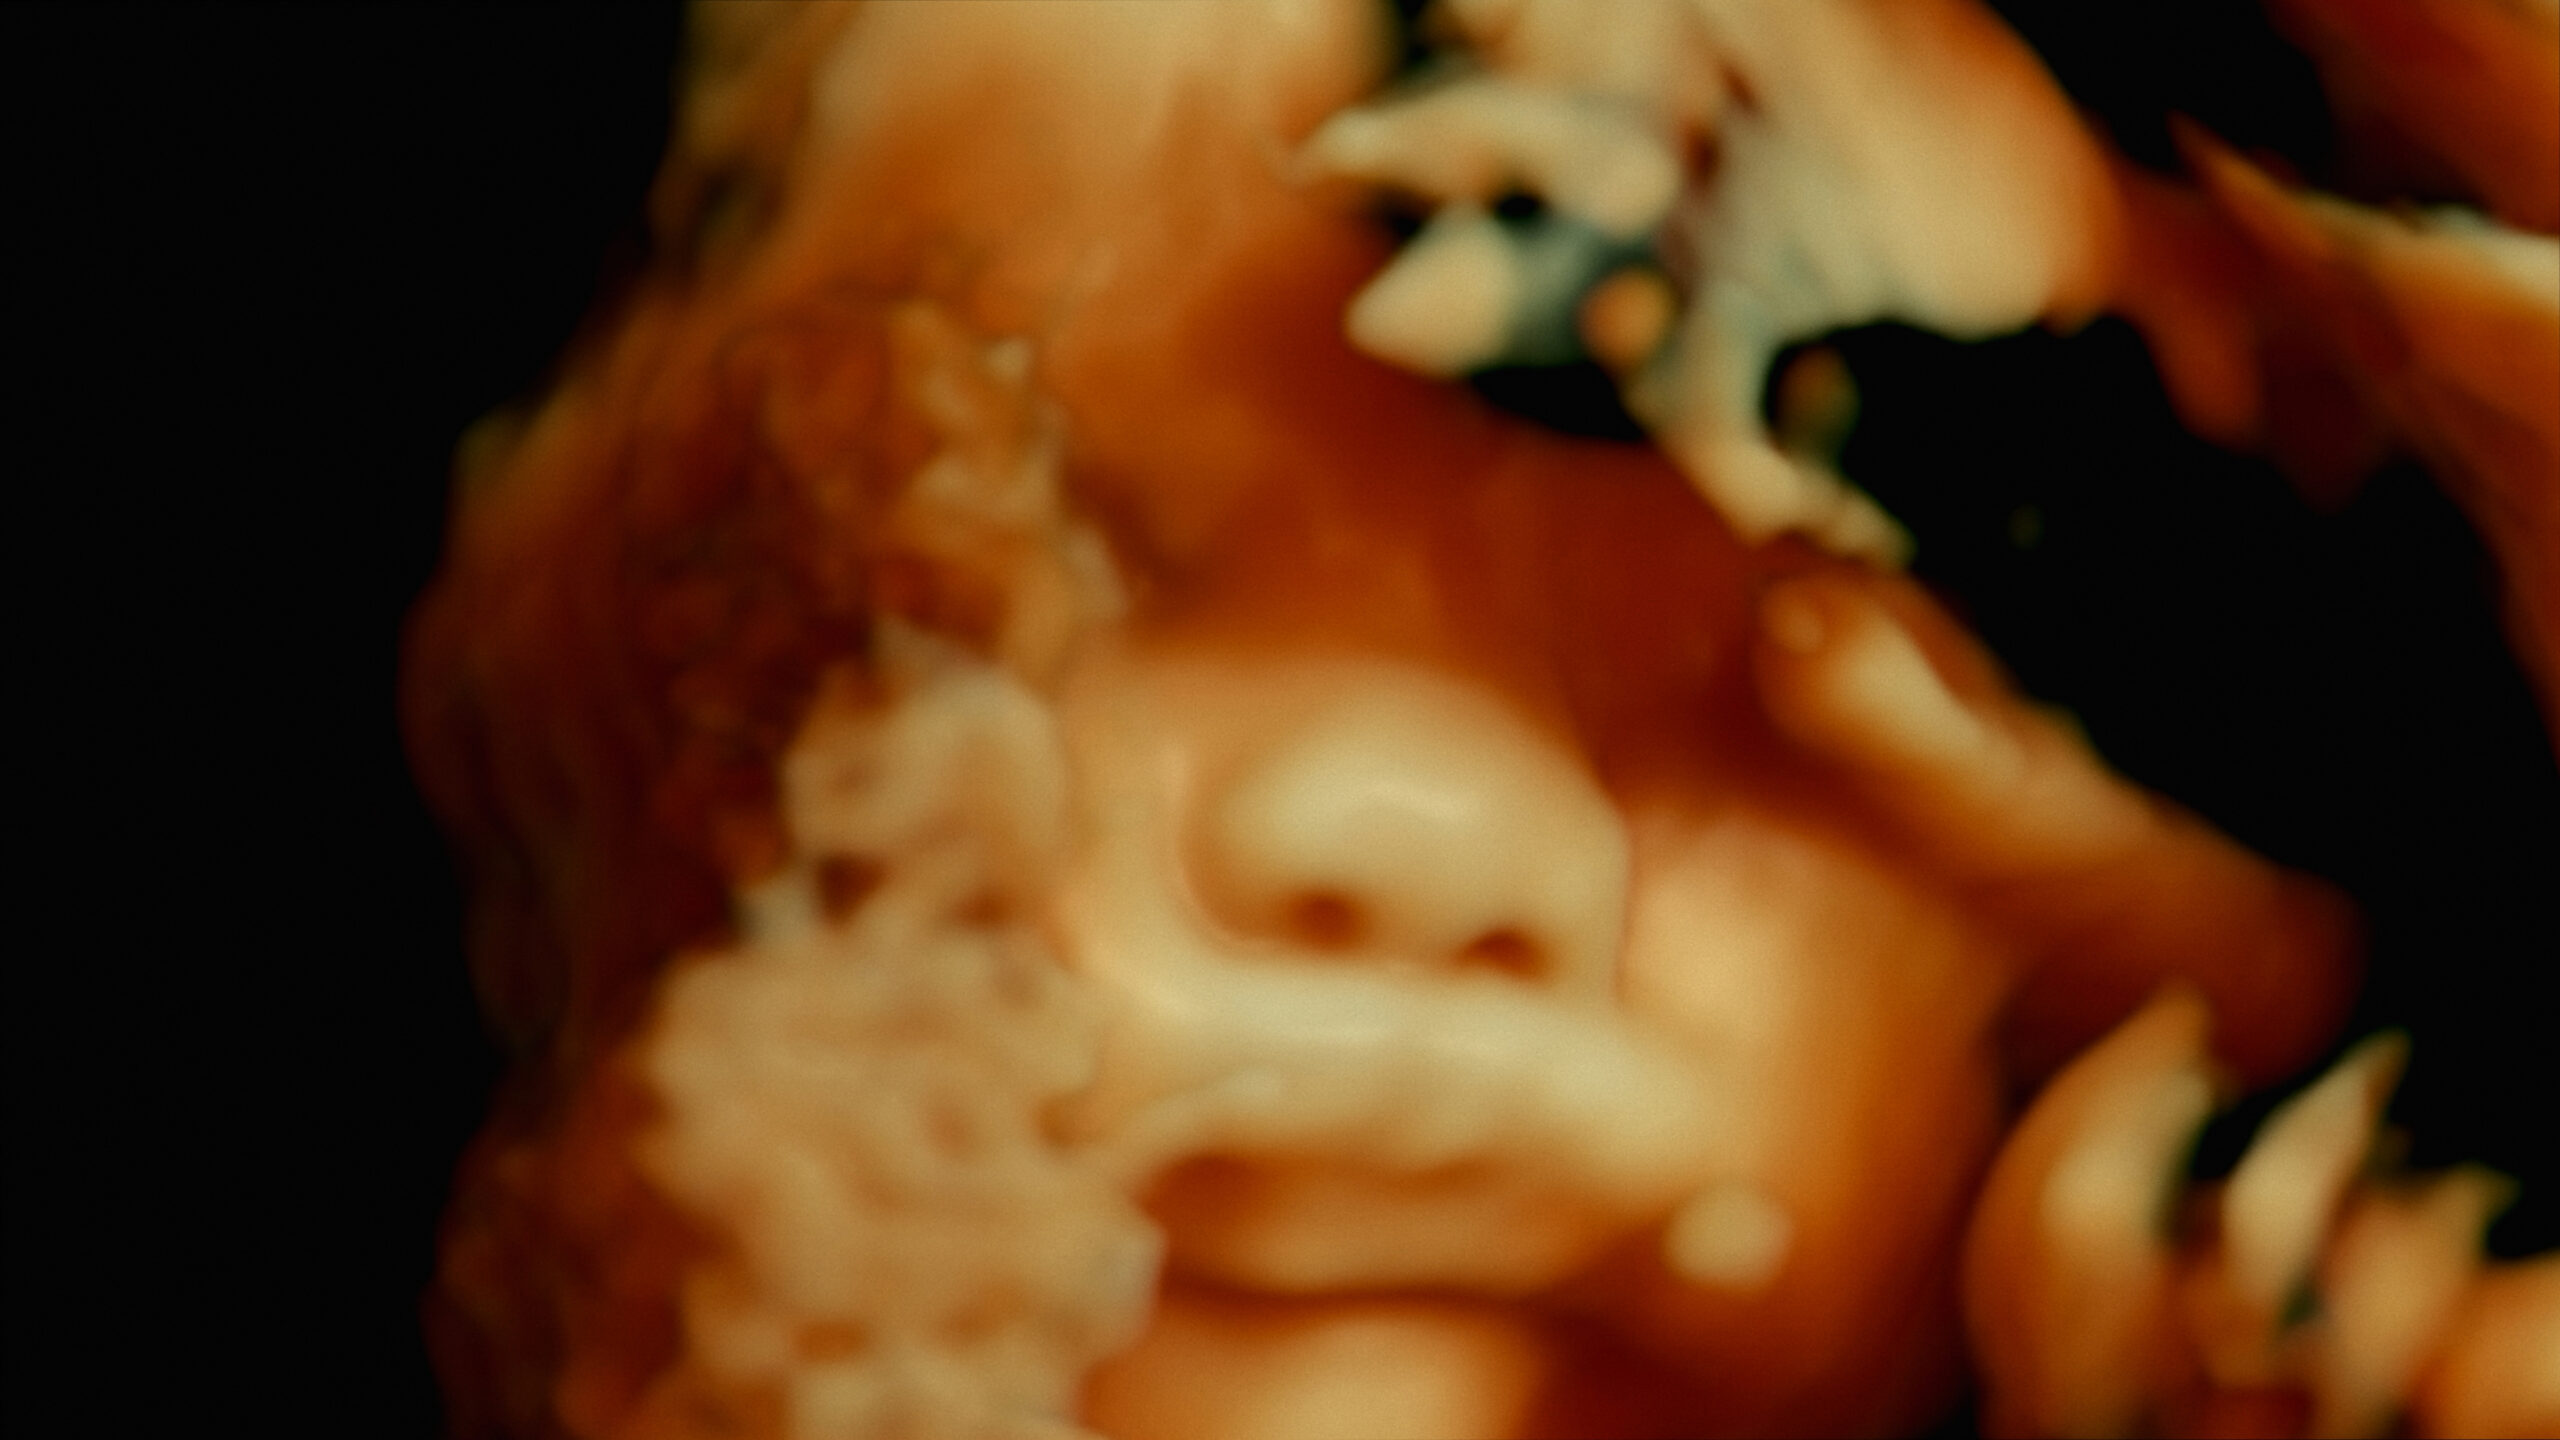

Filmed at five Parisian hospitals, De Humani Corporis Fabrica examines the strain to which the French health system and its staff are subjected, while also diving deep into the human body. The camera shows us in amazing detail the impact of surgical procedures on bones and organs, and the seemingly cool detachment with which the doctors and nurses perform the operations while under enormous stress.